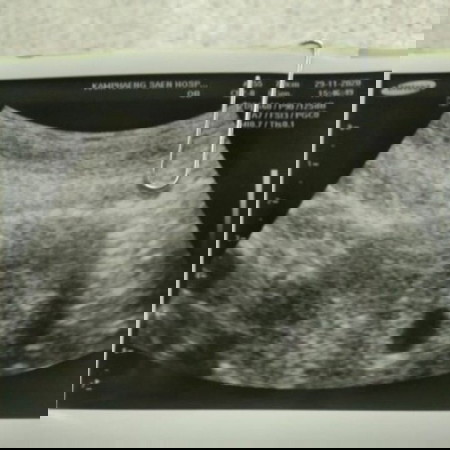

ซาวด์8วิคไม่เจอเหมือนกันคะคุณหมอจะให้ ยุติ การตั้งครรภ์ แต่นัด อีก 2 อาทิตย์ เพื่อซาวด์ดูอีก เลยตัดสินใจหาหมอเฉพาะทางค่ะ สูติ อัลตร้าซาวด์ คลินิก อีกรอบ เจอน้องช่วง 9 + 5 วิก ค่ะ บางทีก็อาจเป็นด้วยเครื่องซาวด์ ที่หมออธิบายนะคะ เพราะว่าเครื่องเอกชนกับรัฐต่างกัน เข้าใจความรู้สึกค่ะ ตอนหมอบอกว่าท้องลม เสียใจไม่ใช่น้อยเหมือนกัน สู้ๆนะคะ ขอให้เจอน้องไวๆค่ะ

ซาวด์ผ่านหน้าท้องหรือช่องคลอดคะ ซาวด์ผ่านช่องคลอดจะเห็นน้องชัดเจนกว่า ลองเปลี่ยนคุณหมอและวิธีการซาวด์ดูก่อนไหมคะ เผื่อน้องยังเล็ก เราก็เคยผ่านเหตุการณ์แบบนี้มาค่ะ เลยอยากแนะนำ เอาให้ชัวร์หลายๆหมอว่าไม่มีน้องจริงๆ อีกวีคลองไปซาวด์ดูใหม่ก็ได้ค่ะ เป็นกำลังใจให้คุณแม่นะคะ😊

ของเราซาวตอน7วีคไม่พบเด็กพบแต่ถุงน้ำคร่ำ ซาวอีกทีตอน14วีค พบเด็กค่ะ คุณแม่อย่าเพิ่งใจร้อนยุติการตั้งครรภ์นะคะ เพราะอายุครรภ์ยังน้อยอาจจะยังไม่พบเด็กค่ะ อดทนรอดูอีกนิดนะคะ เป็นกำลังใจให้ค่ะ

9weeks ก็เห็นแต่ถุงตั้งครรภ์ไม่เห็นน้องเหมือนกันค่ะ หมอนัดอีกทีตอน 10weeks แต่ก็ให้ยาบำรุงไปทานด้วย ตอนนี้คลอดละค่ะ ^^ ใจเย็นๆ นะคะ น้องอาจจะยังตัวเล็กมากๆ